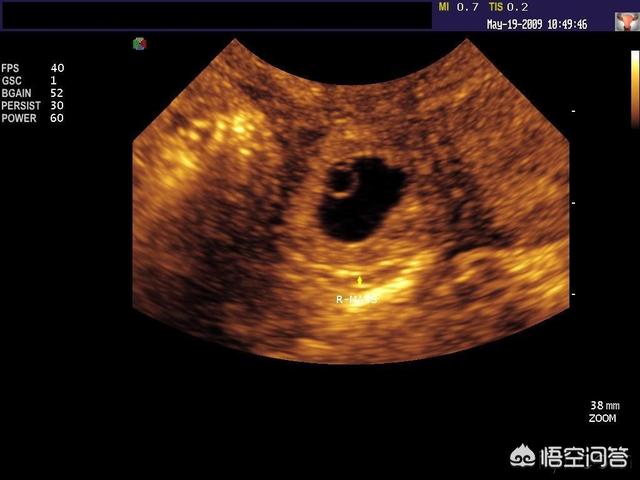

心拍確認できるのはいつから? 妊娠5〜6週(生理予定日より2週間以上すぎたあたり) になると、ほとんどの場合で赤ちゃんの心拍が確認できます。 この時期は妊娠2ヶ月あたり「妊娠初期」になります。 赤ちゃんの心拍は、基本的に「超音波検査」で 胎嚢が確認できるのはいつ? 心拍が確認できるときは、胎嚢はどれくらいの大きさ? 新米妊婦さん向けに「胎嚢」についてお医者さんがわかりやすく解説します。 「胎嚢の確認が遅れていて不安」というプレママの不安にもお答えします。 妖精さんがキタものの流産の確率が高いのもこの時期 心拍が確認されれば流産の可能性もぐんと減りますが 一番不安で仕方ない時期かと思います 「妊娠初期のみ」の不安を存分に語りましょう sage推奨 関連スレは>>2 テンプレは>>28あたり

一般的に、胎嚢は妊娠4週後半~5週頃にかけて確認することができるとされています。 通常は、胎嚢・胎芽・心拍の三つを確認できた時点で、正常妊娠であると診断されます。 ただし、胎嚢が確認できる時期には個人差があります。 初診で確認でき 体外受精の検診で、心拍確認に行ってきました。 2週間前は胎嚢確認までできたので、順調に育っていれば心拍確認ができるはず。 心配で心配で検索魔になりながら2週間過ごしたので、ドキドキでした。 あと、心拍確認私の場合、5週で胎嚢5ミリ、 6週で胎嚢124ミリ 胎芽1ミリ(心拍微弱確認)、 7週で出血が始まり完全流産でした。 初めての妊娠だったのですが、つわりは最初からあまりなく、またお腹が頻繁に張っていたように思います。